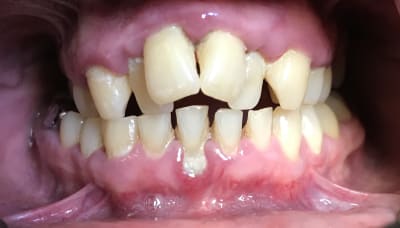

En attendant que le nouveau réponde ... Dans un style différent : 38 ans . très complexé. Aucun dentiste n’a voulu le toucher (pour le secteur antérieur) . Je lui ai dit qu’il fallait lui déglinguer la mâchoire. Sauf qu’il ne veut pas faire de chirurgie orthognatique, c’est sa seule condition . Par contre est prêt à mettre n’importe quel prix pour retrouver un beau sourire. N’est ni fermé à l’ortho , ni fermé à l’implantologie.

Photo de la pano qu’il m’a ramenée.

On se passera des : faut faire un détartrage :) , ou faut qu’il se lave les dents.

Ex des centrales et bridge 12-22, je pense que tu peux faire un truc sympa. Teste sur ton plâtre.

Mouais, mouais, mouais... Très complexé... Le problème, c'est que ça se limite pas qu'au dent...

Pour moi, ortho, orthopédie ou rien. J'aime bien rien.

c'est clair que tu peux faire un truc sympa

à condition de maitriser l'hygiene avant tout et de preserver les canines à tout prix

et à condition que l'occlusion soit bien tolérée examen soigneux des ATM et des muscles masticateurs

la seule solution esthétique pour ne pas lui faire des contrales de lapin passe par une fausse gencive

40 ans d'expérience me disent qu'aucune soltion fixe ne serait durable

38 ans ?? Je lui en donne 55...

Le cas du début c'est avant tout une supraclusie carabinée.

Faut voir si il serre les dents, comment il respire et deglutit....

Gouttières dures chiadées oclusalement, le lieux étant qu'il puisse bouffer avec.

Comme ça tu peux remonter en postérieur et te donner une chance de réhabiliter devant.

Si et seulement si il supporte alors restaurations résine en postérieur et devant ensuite.